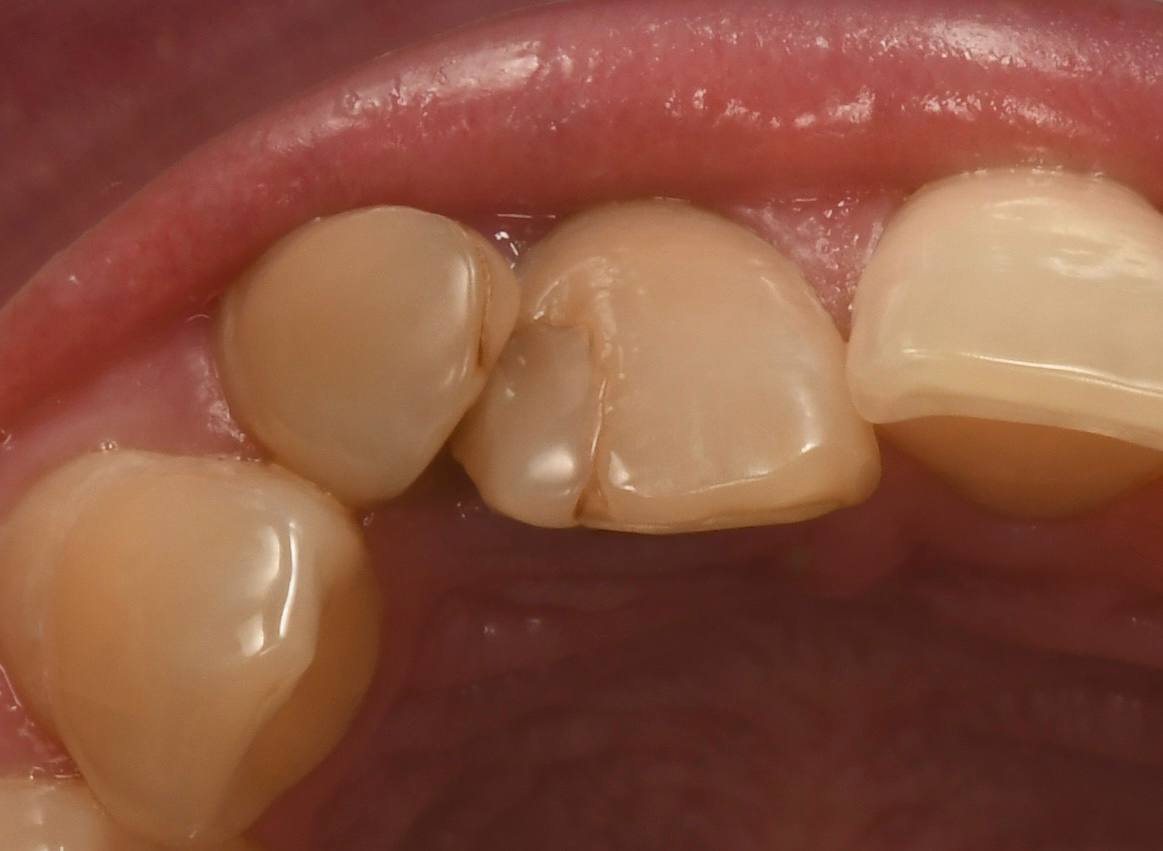

Лечение кариеса и восстановление формы зуба - просто шедевральная работа. Все никак не налюбуюсь своим зубом, уж очень красивый!! Спасибо!!!

Неудобства при жевании, не нравится моя улыбка и форма зубов